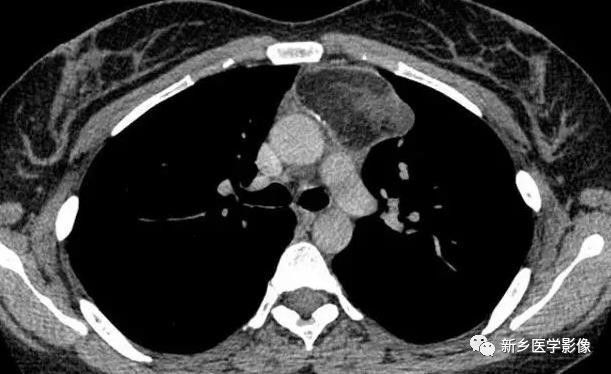

侵袭性胸腺瘤CT图像

a. CT平扫示肺动脉与胸骨间肿块,密度尚均匀,形态不规则b. CT增强示肿块不均匀强化,见低密度囊变区域,肿块与肺动脉之间脂肪间隙消失,肺动脉壁模糊。